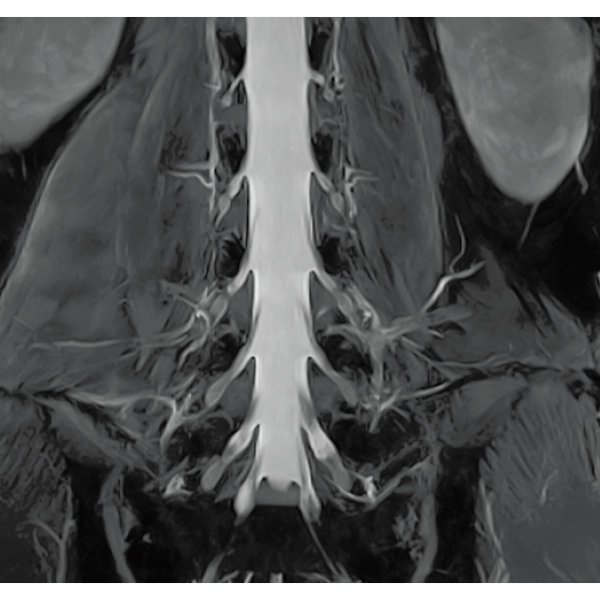

"DLR" is applicable to all body parts and promotes high speed imaging and diagnostic efficiency

IP-RAPID x DLR Plus can also shorten imaging time, allowing more images to be taken in the same examination time.

Additional imaging, such as different image types and cross sections, can be added to the conventional examination to increase the amount of information and make the diagnosis more reliable.

IP-RAPID x DLR Plus gives you the flexibility to shorten respiratory gated series or even replace them with breath-holds, depending on the patient’s situation. This gives you more options and a wider range of examinations to choose from.

IP-RAPID x DLR Plus can be used for basic imaging such as VolumeScan, RadialScan, HalfScan, and many other imaging methods such as MultiContrastScan FatSep and DWI.

It can also be used with time-consuming scans such as Whole Body DWI and Whole Spine imaging, providing more detailed information in many areas than previously possible.